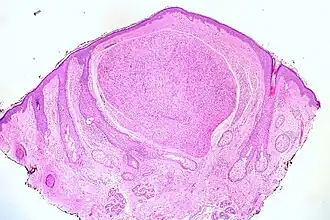

Een neuroom, ook wel neurinoom is een kleine, goedaardige woekering van zenuwweefsel die ontstaat op een plaats waar een zenuw beschadigd is, doordat de zenuwuitlopers blijven groeien in een poging hun aansluiting te hervinden maar daarvoor geen richting hebben. Hierbij ontstaat een kluwentje van zenuwvezels dat vaak als een enkele mm groot bobbeltje voelbaar is en meestal bij aanraking een gemene pijnscheut veroorzaakt. (Als hij geen pijn zou veroorzaken wordt een dergelijke kleine afwijking in het algemeen niet eens opgemerkt).